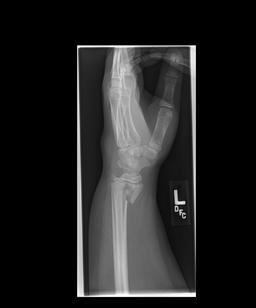

4th or 5th MCP

Bar room facture

2nd or 3rd MCP

fracture

Boxer’s fracture